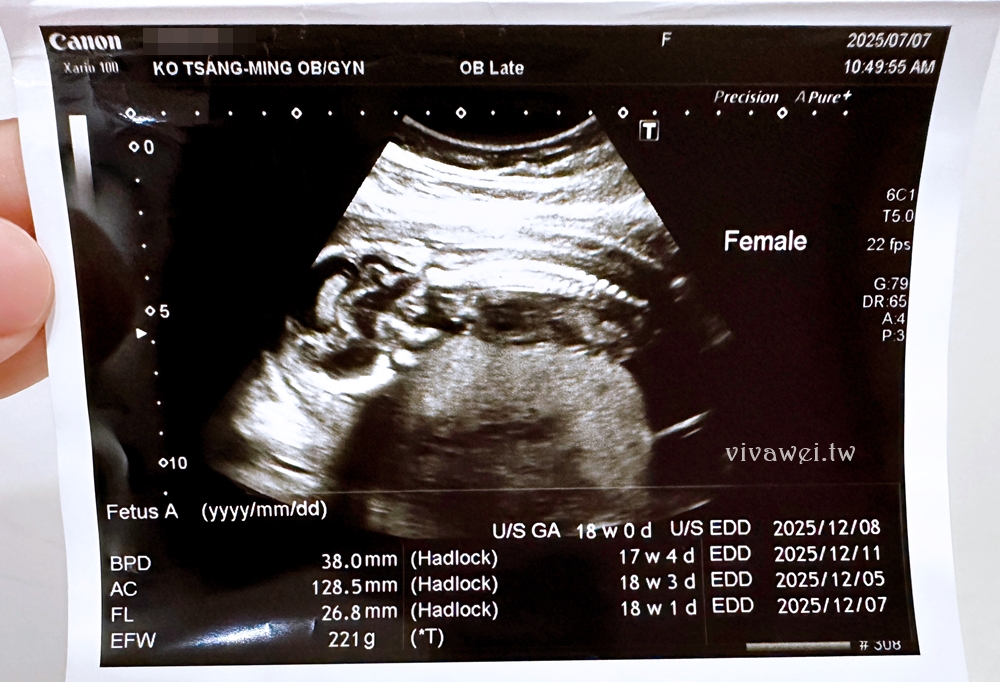

▲當日是由一位柯藥師進行問診,會問近期產檢有沒有遇到什麼狀況,有沒有出血的問題,也會簡單說明羊膜穿刺和羊水晶片檢查的內容項目!接著會安排到超音波室由護理人員協助照超音波,會在照超音波的時候確認性別、寶寶的心跳、羊水量等!

▲羊水晶片結果正常:正常女性基因體組合,未發現致病性的DNA片段增加或減少!

▲羊膜穿刺報告正常:46,XX,正常女性染色體群組。